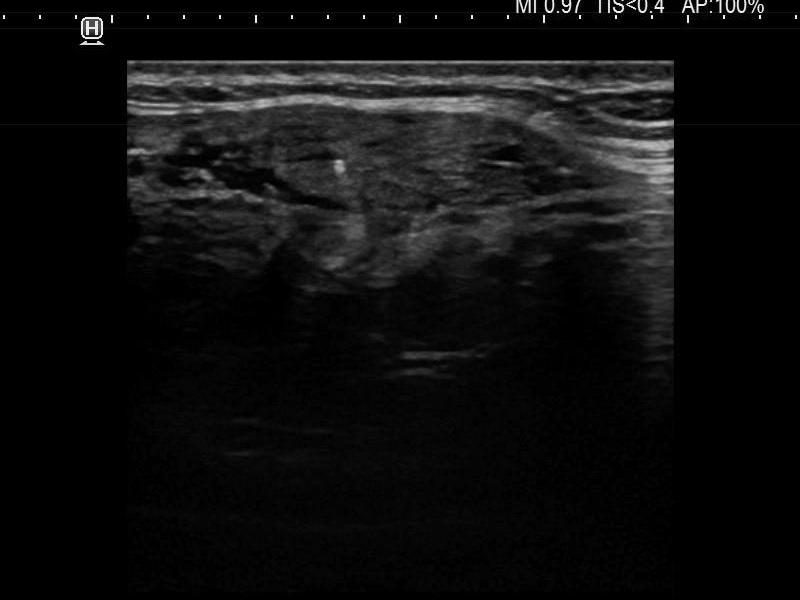

Ultrasonography. The thyroid was moderately hypoechoic and presented with numerous more and less hypoechoic discrete lesions. The largest of the latter was in the lower ventromedial part of the left lobe and had cystic areas and intranodular echogenic figures. The latter included typical comet tail artifacts, back wall cystic figures and some ambiguous small bright granules. The lesion showed both perinodular and intranodular vascularity. Compared with the former examination the nodule increased by 22% in volume. This difference is within the intraobserver variation.

Comment. Based on the presence of typical comet-tail artifacts, the questionable punctate echogenic granules are worth considering also colloid crystals.